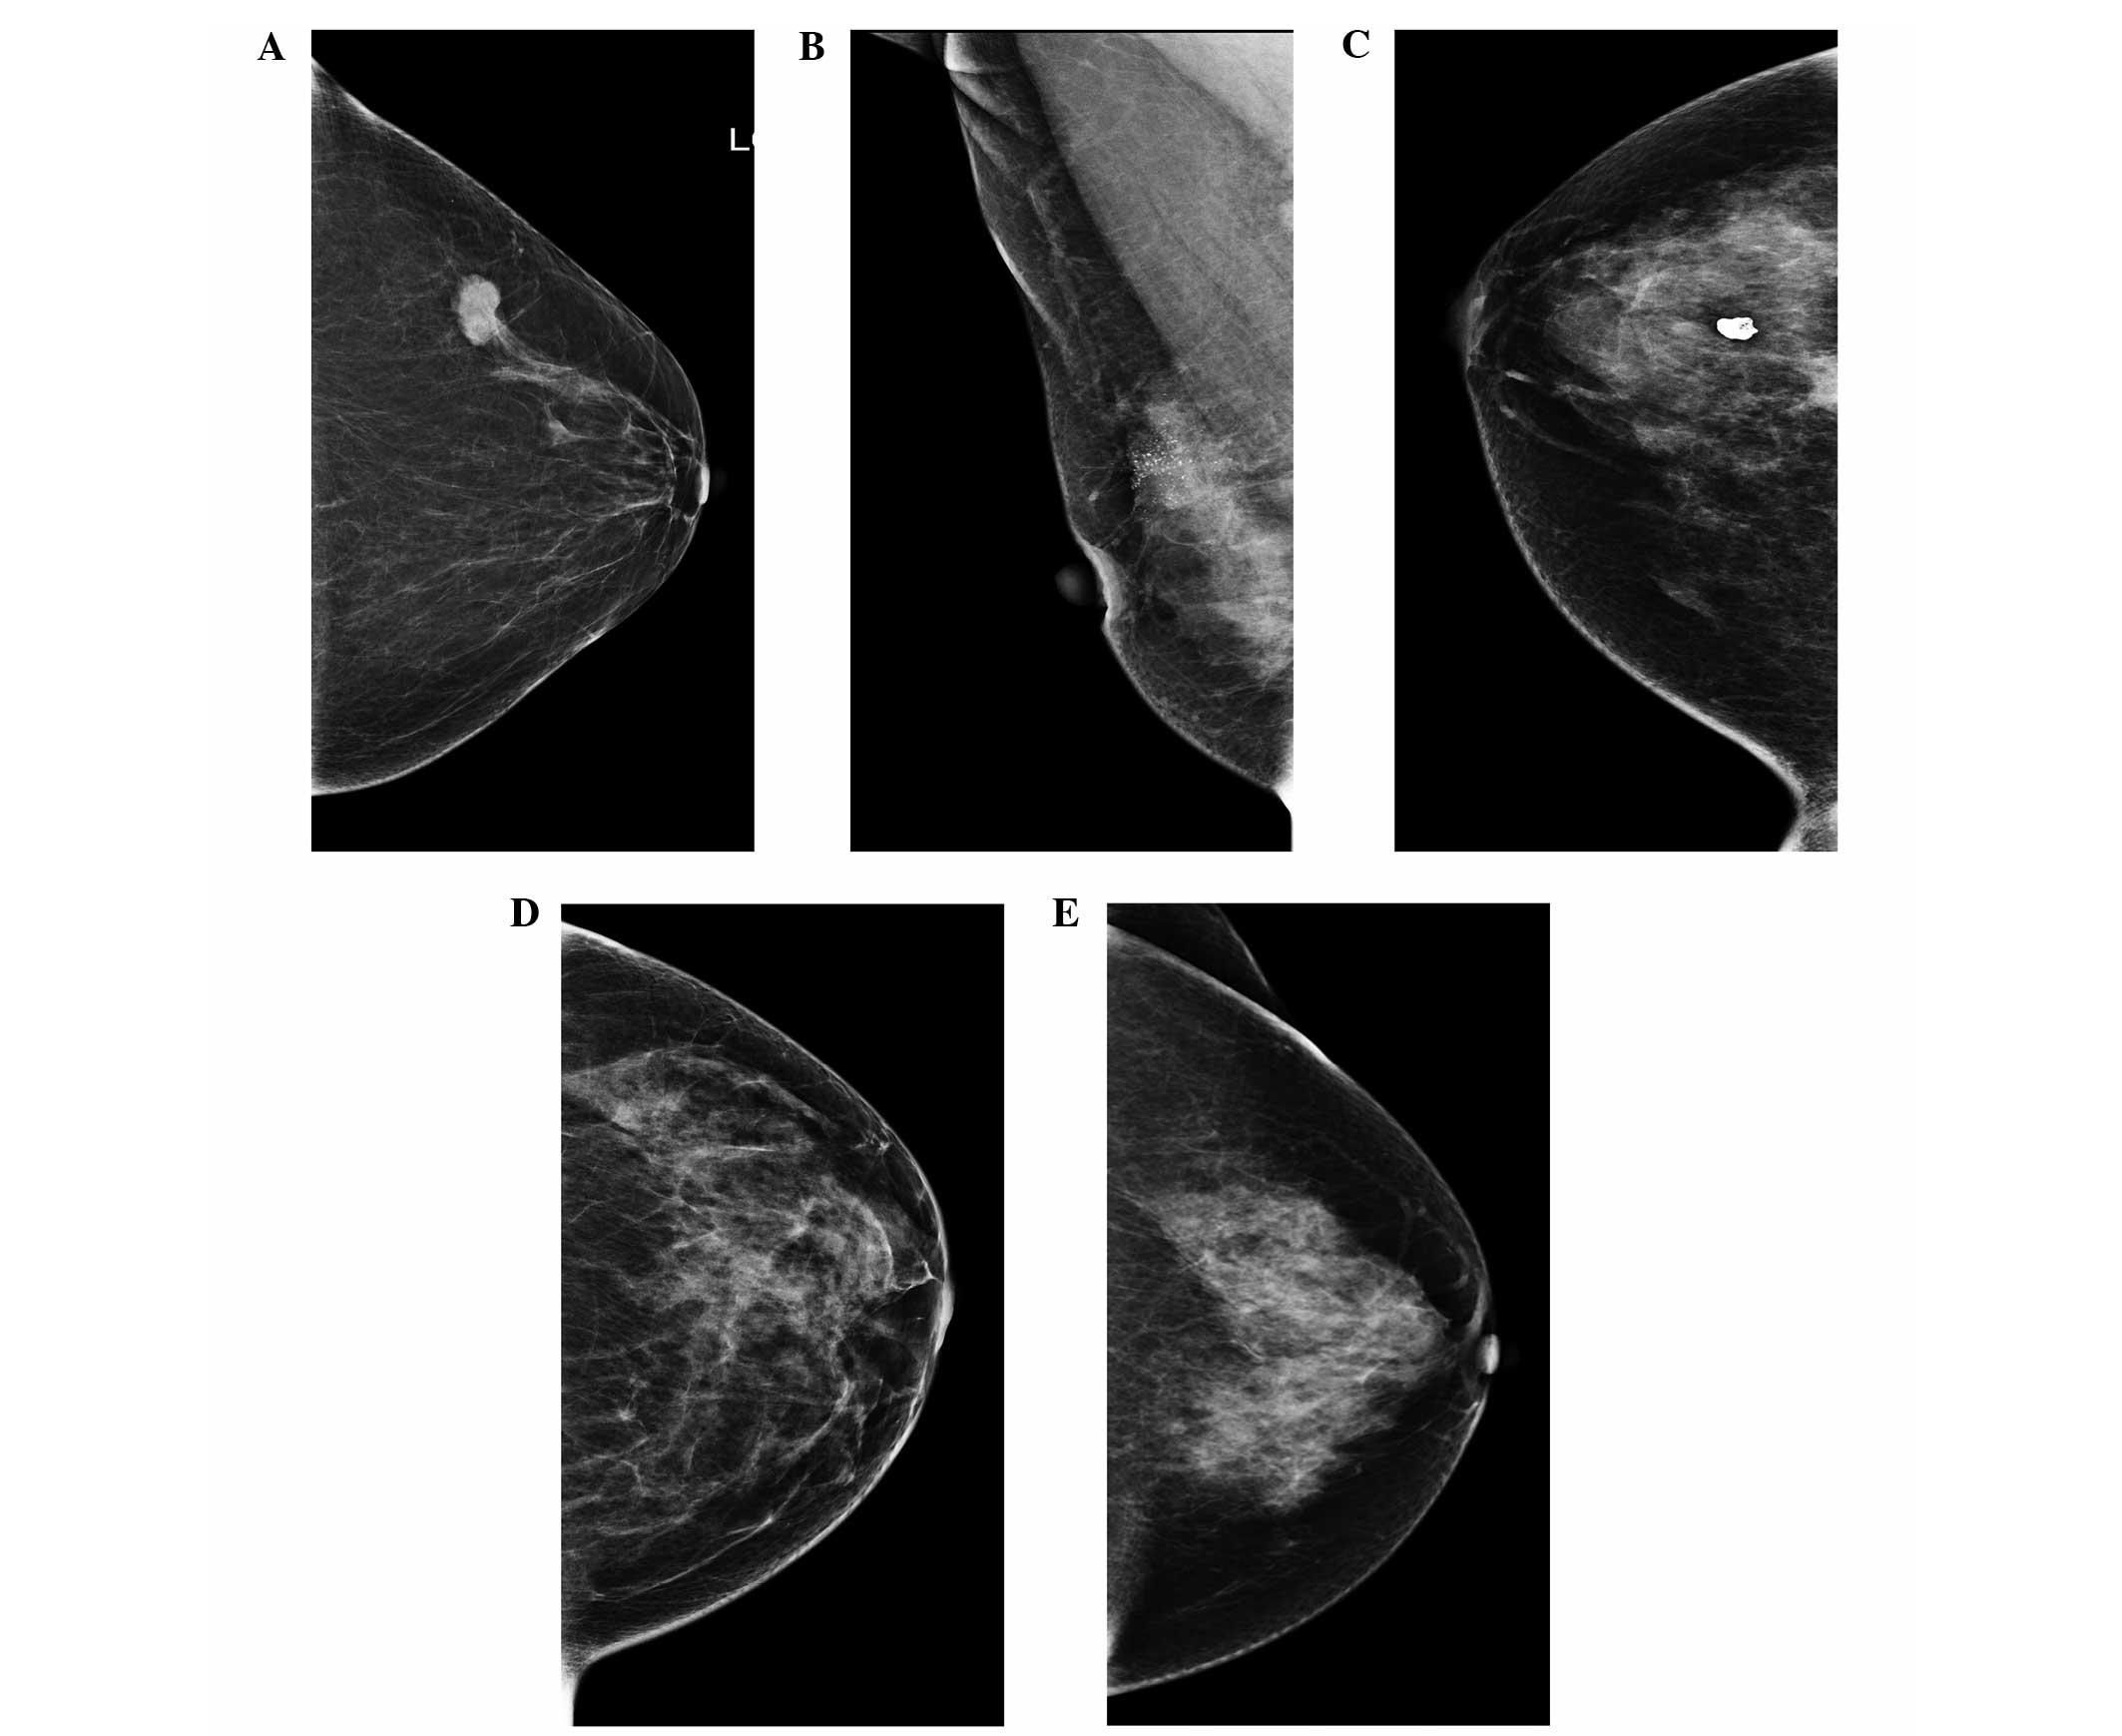

The developing asymmetry has a 1215 risk of malignancy but poses challenges of detection and interpretation due to the lack of typical features of cancer and the frequent absence of an ultrasound correlate. Currently magnetic resonance MR imaging does not have a recognized role in the assessment of breast asymmetry. Should I be worriedRead 1 Responses.

Exercise Architectural Distortion And Asymmetric Density The Asymptomatic Patient